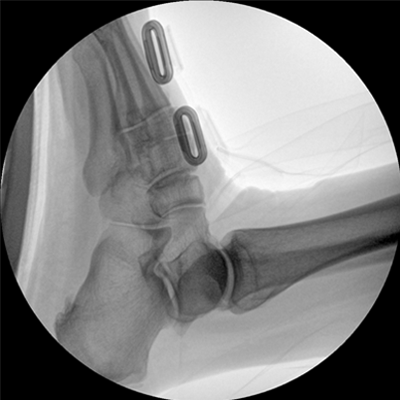

專業(yè)的圖像處理系統(tǒng),為您提供高分辨率、高灰階圖像。